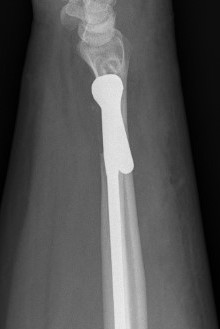

Aptis DRUJ total joint arthroplasty

Dorsal approach

- between 5th and 6th extensor compartment

- open extensor retinaculum

- resect proximal ulna

- prepare radius and apply radial plate checking implant position with fluoroscopy

- intramedullary ream ulna

- press fit ulna prosthesis